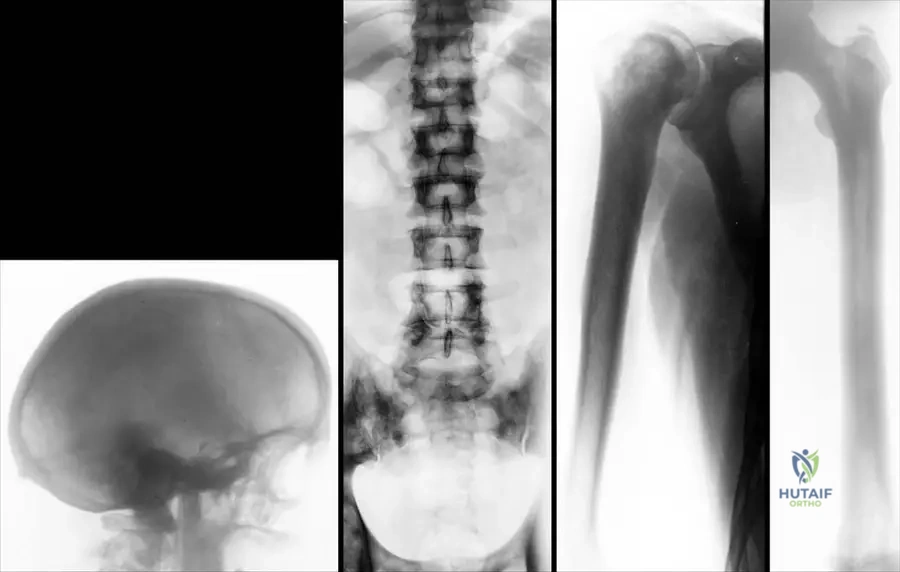

Rationale: The image description (Fig. 1.113a) and the text for the late form of osteopetrosis specifically mention that "The base of the scull is thickened and sclerotic." This bone overgrowth can contribute to headaches and visual disturbances by narrowing foramina. The main distractor, thinning of the skull vault, is incorrect as osteopetrosis is characterized by increased bone density and thickness, not thinning.

Rationale: Figure 1.113a, which depicts the late form of osteopetrosis, shows that "The base of the scull is thickened and sclerotic." This is a characteristic finding due to the generalized osteosclerosis. Enlarged sella turcica (A), multiple lytic lesions (B), premature suture closure (D), and thinning of the calvarium (E) are not described as typical findings for the skull in osteopetrosis in the provided text or images.

Correct Answer: B

Rationale: Figures 1.113c and 1.113d, showing the humerus and distal femur in the late form of osteopetrosis, state that "the medullar cavity is narrowed but present." This indicates that while the bone is denser and the cavity is reduced, it is not completely absent. Completely obliterated (A) is too extreme. Widened (B), filled with lytic lesions (D), or normal (E) are contrary to the described radiographic findings.